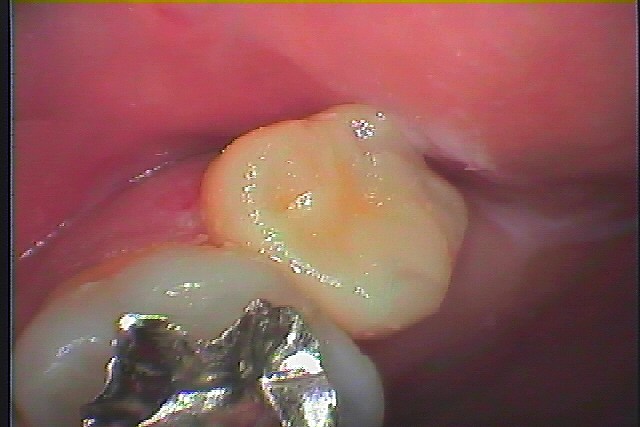

銀歯を外してセラミックを入れていきます 審美治療 40代女性|お知らせ |広島市安佐南区の歯科医院 銀歯を外してセラミックを入れていきます 審美治療 40代女性 トップ お知らせ・ブログ お知らせ 銀歯を外してセラミックを入れていきます 審美治療 40代女性 銀歯を外してセラミックを入れていきます 審美治療 40代女性 この銀歯を外していきます 境眼が黒く虫歯になって生きています 外したところになります CR樹脂にて覆罩を行っていきます セレックセラミックにて綺麗に修復しました 左上7番の銀歯を外していきます 虫歯を除去していきました セレックセラミックにてきれいに修復しています Web診療予約 初めての方へ 選ばれ続ける理由 院内設備について 歯が痛いしみる一般歯科 歯がぐらぐらする歯周病 健康な歯を保ちたい予防歯科 子供の虫歯予防をしたい小児歯科 銀歯をセラミックに審美歯科 白い歯を目指しませんか?ホワイトニング 矯正専門医がいるので安心矯正歯科 抜けた歯を補いたいインプラント・入れ歯 医院案内 スタッフ紹介 メリィハウス歯科クリニックオフィシャルホームページ ラベンダー歯科クリニックオフィシャルホームページ お知らせ・ブログ ホーム 診療科目 一般歯科 歯周病治療 予防治療 小児歯科 審美治療 ホワイトニング 矯正歯科 入れ歯・インプラント マウスピース矯正 初めての方へ 院長・スタッフ 設備紹介 医院案内・アクセス メニューを閉じる